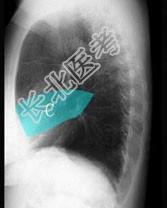

- 单项选择题在图所示正常胸部X线影像图像上,该英文字母所代表的肺段为 ( )

A、尖段

B、后段

C、尖后段

D、舌叶上段

E、前段